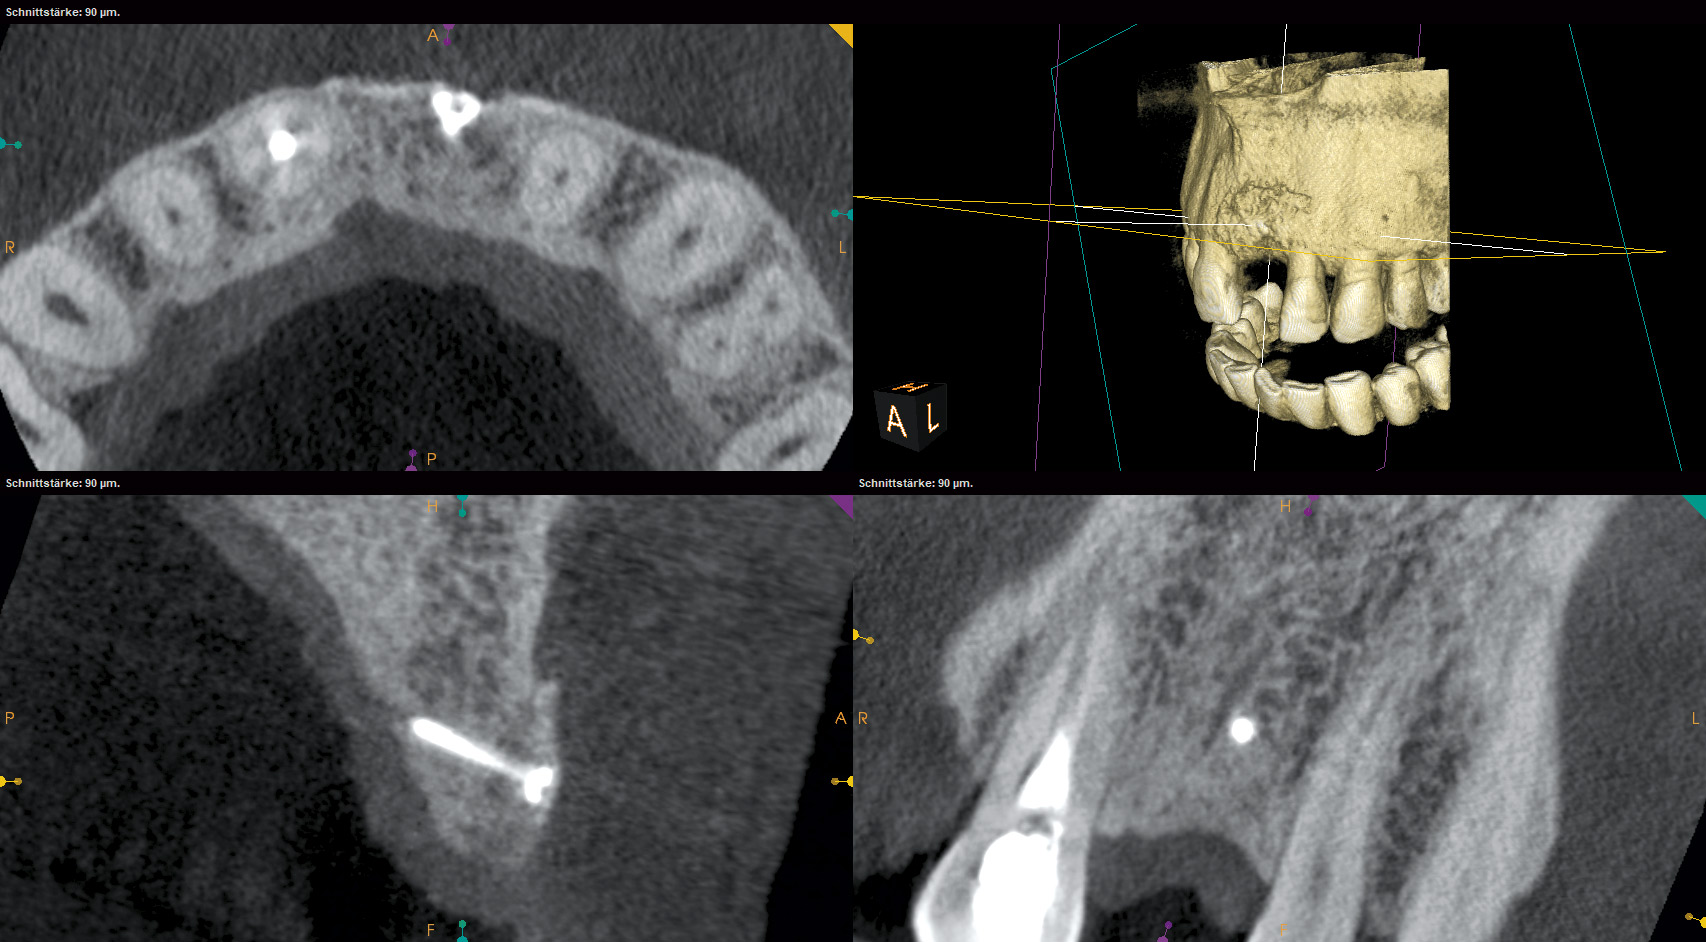

14/18 - CBCT scan after implantation

Block augmentation with maxgraft® and cerabone® – PD Dr. Dr. F. Kloss